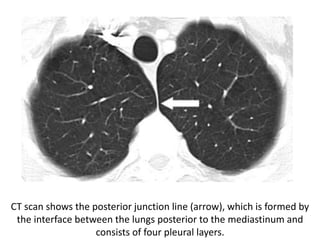

CT scan shows the posterior junction line (arrow), which is formed by

the interface between the lungs posterior to the mediastinum and

consists of four pleural layers.